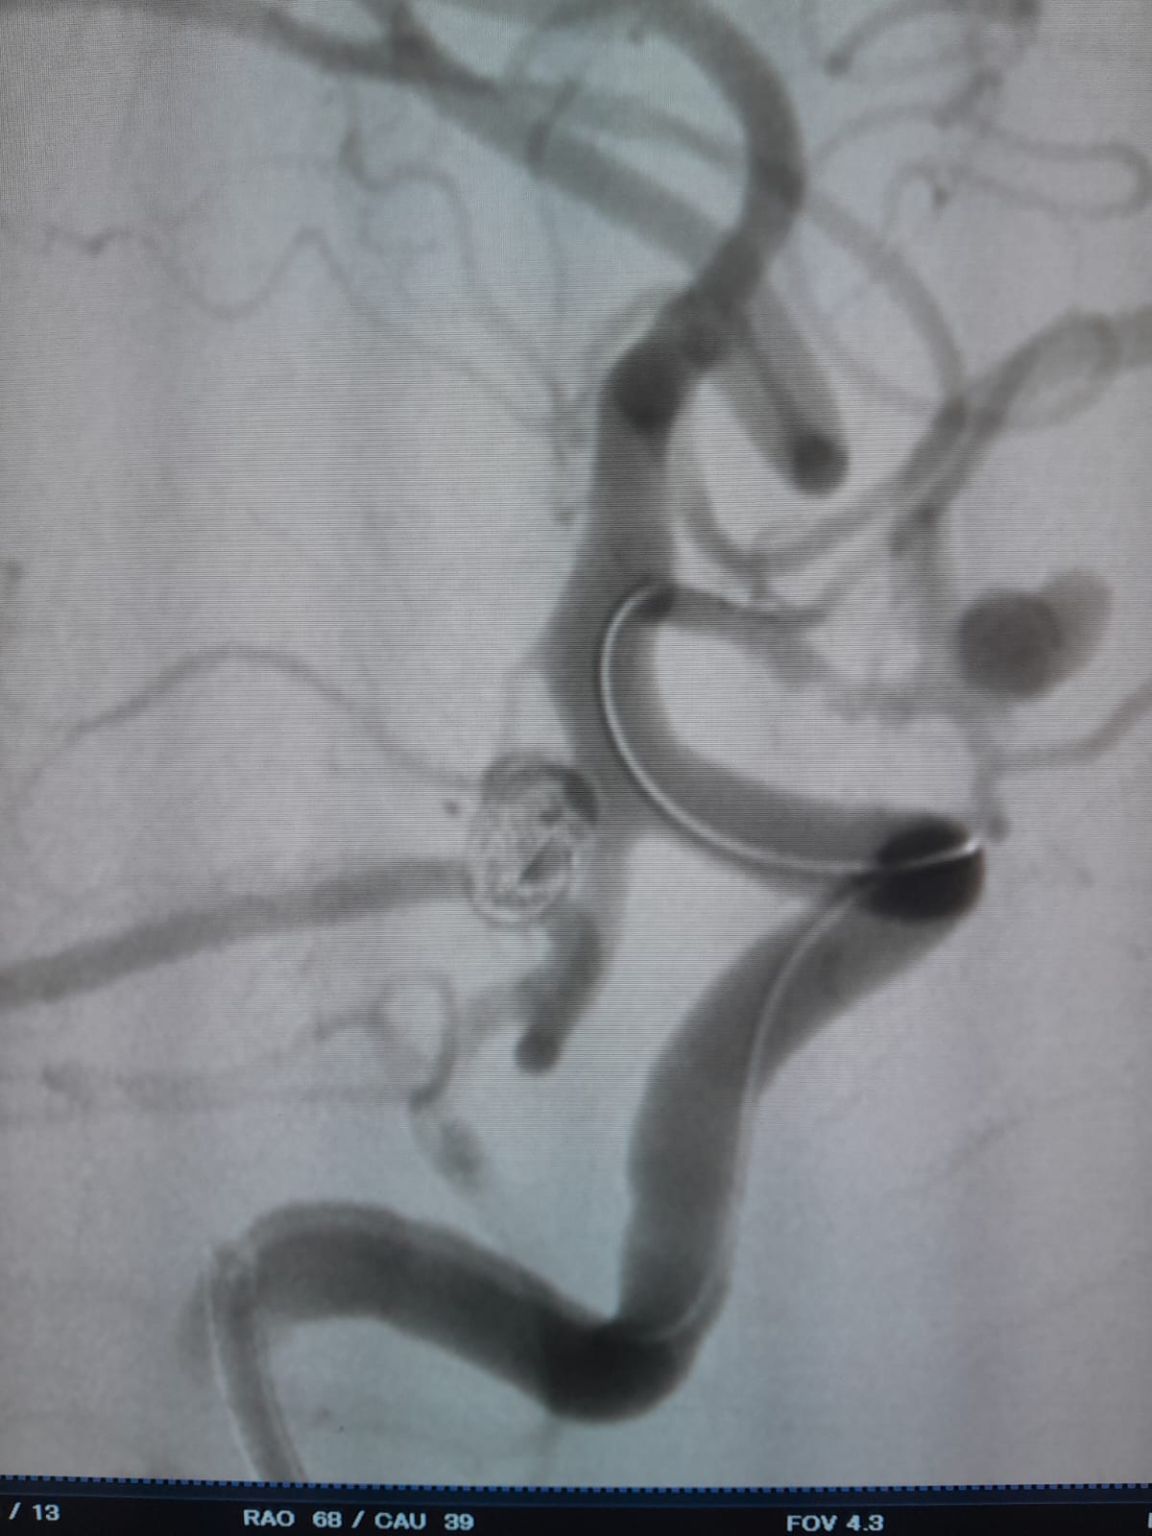

O paciente foi diagnosticado com um aneurisma sacular da artéria comunicante anterior (AComA) recentemente descoberto e um aneurisma da artéria comunicante posterior (PComA) previamente tratado com embolização por bobina. Imagens de acompanhamento revelaram preenchimento residual no aneurisma do PComA, necessitando de intervenção adicional.

Durante o acompanhamento, observou-se enchimento residual no aneurisma da artéria comunicante posterior previamente tratado. A equipe acessou novamente o site usando o Frepass®Microcateter descartável (TJMC18 Plus) e implantado com sucesso um Nuva®Desvio do fluxo (TJED-D-4.5-16), que demonstrou a aposição ideal da parede e o desvio excelente do fluxo, conduzindo aos resultados altamente satisfatórios do tratamento.